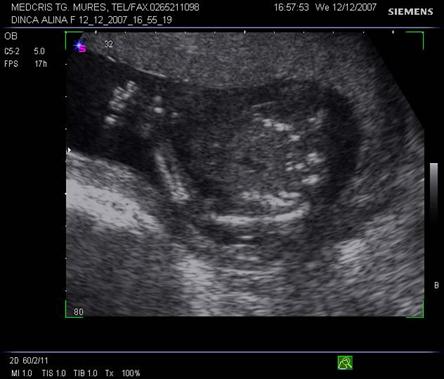

Evaluarea structurilor specifice in sectiunea 4 camere

Atriul stang - valva de la foramen ovale (septum primum) floteaza ritmic in acest atriu. Venele pulmonare se dechid in atriul stang, iar acesta in ventriculul stang, spre apexul cardiac.

Ventriculul stang are forma ovalara, cu lumenul extins spre apexul cardiac, nu are trabecule tipice in miocard si valva mitrala este mai jos inserata fata de tricuspida (mai spre apex).

Atriul drept comunica prin foramen ovale cu atriul stang. Nu contine valva de la foramen ovale si apare mai mare decat atriul stang. Inferior de atriul drept si aproape de septul interatrial, apare terminarea venei cave inferioare cu valva lui Eustachio, ce are imagine de vas rotund. Atriul drept se deschide spre ventriculul drept.

Ventriculul drept - forma relativ rotunda si se distinge de cel stang prin 5 caractere:

Septul ventricular - apare ca o sageata de 2-4 mm, continuu.

Septul atrial - central intrerupt de foramen ovale, cu o valva batanta